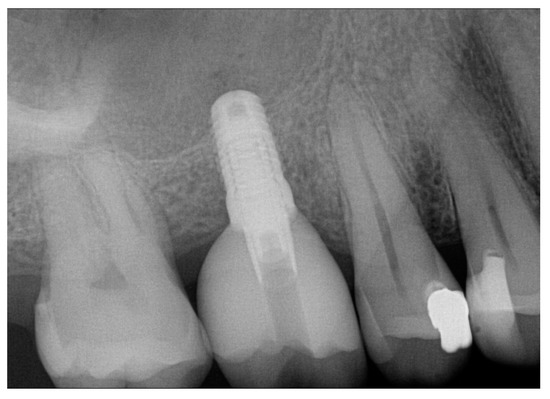

Question 1: What materials cannot be seen in the print of the X ray?

Question2: Which surface shows overhang?

Question 3: Which option is not evident on the print of the X ray?

Question 4: Which options cannot be seen in the print of the X ray?

Question 5: What options cannot be selected for tooth # 4.6?

Question 6: What options cannot be seen in the print of the X ray?

Question 7: What option cannot be identified on the print of the X ray?

Question 8: What condition can be seen in the X ray?

Question 9: Which option cannot be seen in the lower jaw?

Question 10: Which option can be selected for the following X ray?